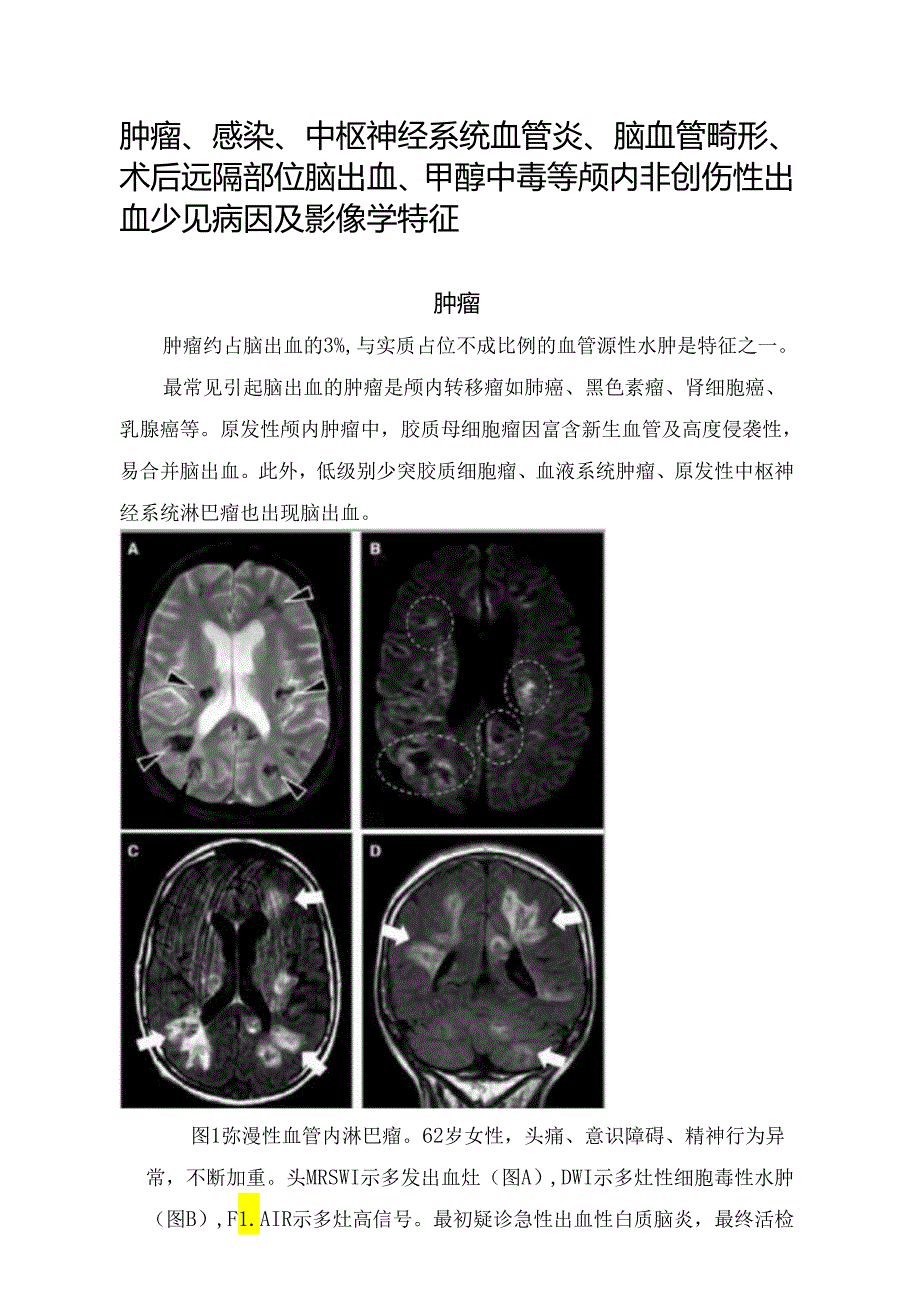

1、肿瘤、感染、中枢神经系统血管炎、脑血管畸形、术后远隔部位脑出血、甲醇中毒等颅内非创伤性出血少见病因及影像学特征肿瘤肿瘤约占脑出血的3%,与实质占位不成比例的血管源性水肿是特征之一。最常见引起脑出血的肿瘤是颅内转移瘤如肺癌、黑色素瘤、肾细胞癌、乳腺癌等。原发性颅内肿瘤中,胶质母细胞瘤因富含新生血管及高度侵袭性,易合并脑出血。此外,低级别少突胶质细胞瘤、血液系统肿瘤、原发性中枢神经系统淋巴瘤也出现脑出血。图1弥漫性血管内淋巴瘤。62岁女性,头痛、意识障碍、精神行为异常,不断加重。头MRSWI示多发出血灶(图A),DWI示多灶性细胞毒性水肿(图B),F1.AIR示多灶高信号。最初疑诊急性出血性白质脑

2、炎,最终活检证实为弥漫性B细胞淋巴瘤。感染当脑出血患者合并感染证据时,应警惕感染继发脑出血的可能(图2)。神经系统受累是感染性心内膜炎最常见的心外并发症;其中,脑出血仅次于脑梗死排第2位。单纯疱疹病毒脑炎(常见)、脑脓肿、真菌性动脉瘤、细菌性脑膜炎(约1.9%)也可出现脑出血。图2感染性心内膜炎合并脑出血。53岁患者,疲劳、发热,确诊感染性心内膜炎。突发右额顶脑出血、枕部出血、蛛网膜下腔出血(图A),大脑中动脉M2段狭窄(图B,白箭头),可见管壁强化(图C),CTA(图D)及MRA(图E)可见不规则真菌性动脉瘤(箭头),枕部血肿内可见真菌性动脉瘤强化影(图F)o中枢神经系统血管炎中枢神经系统血